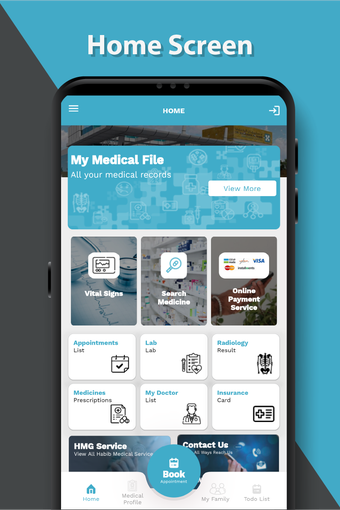

ドクター・スライマン・アル・ハビブ・メディカル・サービス・グループHMGによるAndroid用の無料アプリ。

これは、Dr. Sulaiman Al-Habib Medical Services Groupが提供するすべてのサービスにアクセスするのを助ける無料のアプリです。グループの持続的なデジタル変革の重要な部分であり、効率と生産性の向上を重視しています。この新しいアプリは、オンライン医師相談から医療検査や放射線学の報告書まで、グループが提供するすべてのサービスに簡単にアクセスできるようになります。また、あなたと家族の医療記録を閲覧する機会も提供しています。